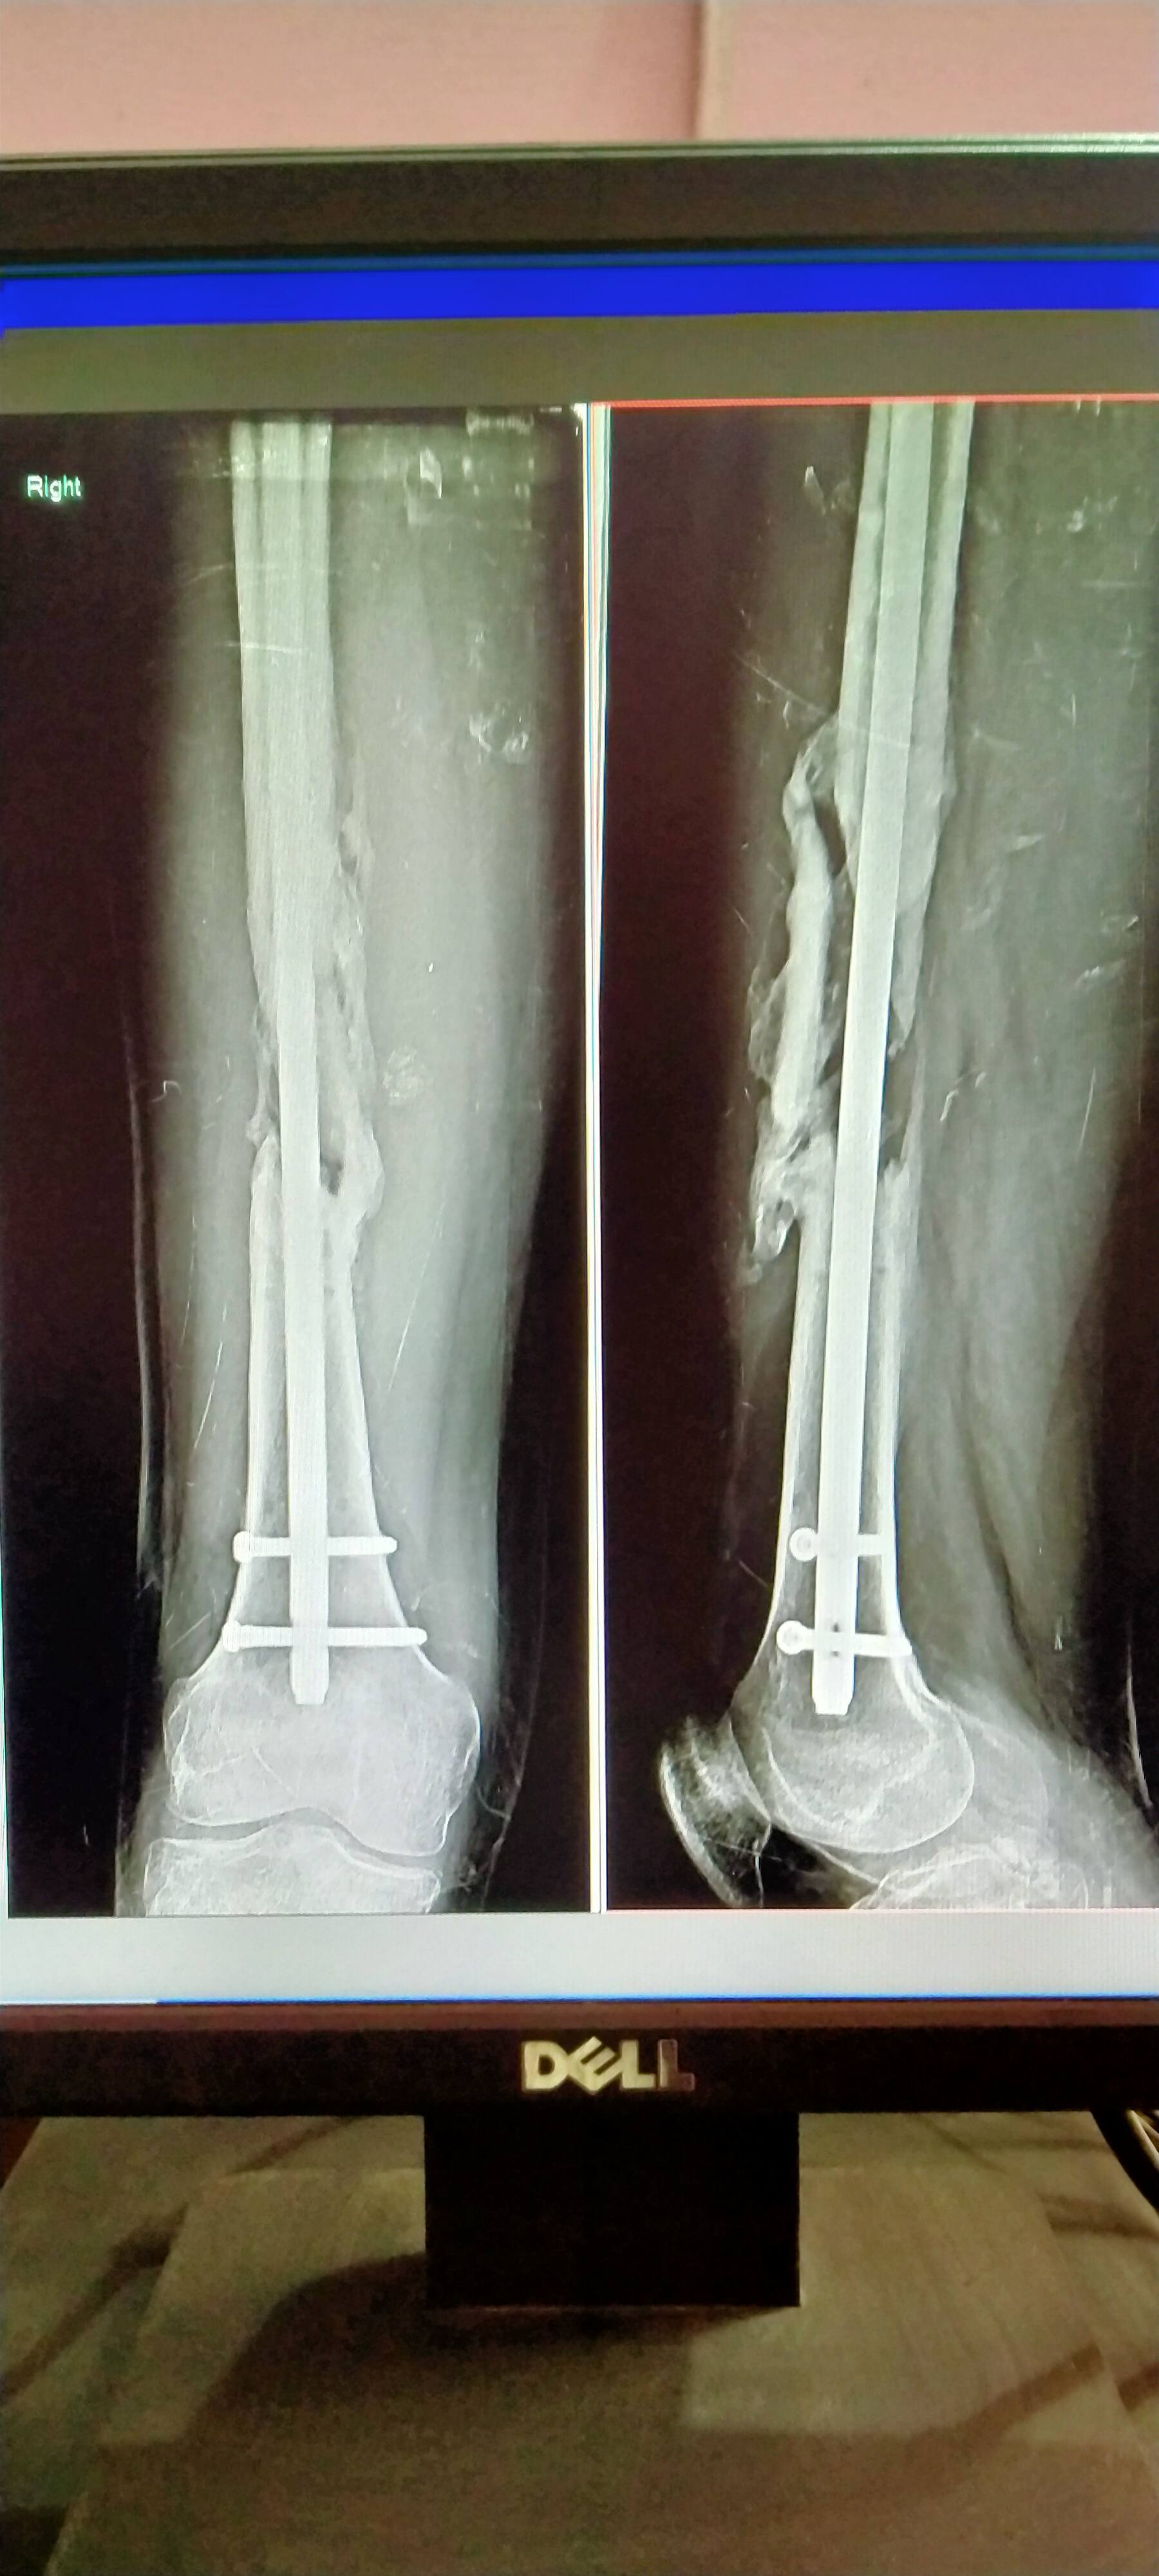

Nhi sahab kuch nhi hua tha phle ek or opresan krwaya tha ,,yr opresan shi nhi hua ,,aab dusra opresan Apollo hospital guwahati me hua h ,, aab aap btao Esme bone add hone me kitna time lagega ,, guwahati Wale doctor bol rhe ki 2 month or lgega but aap btao please sir